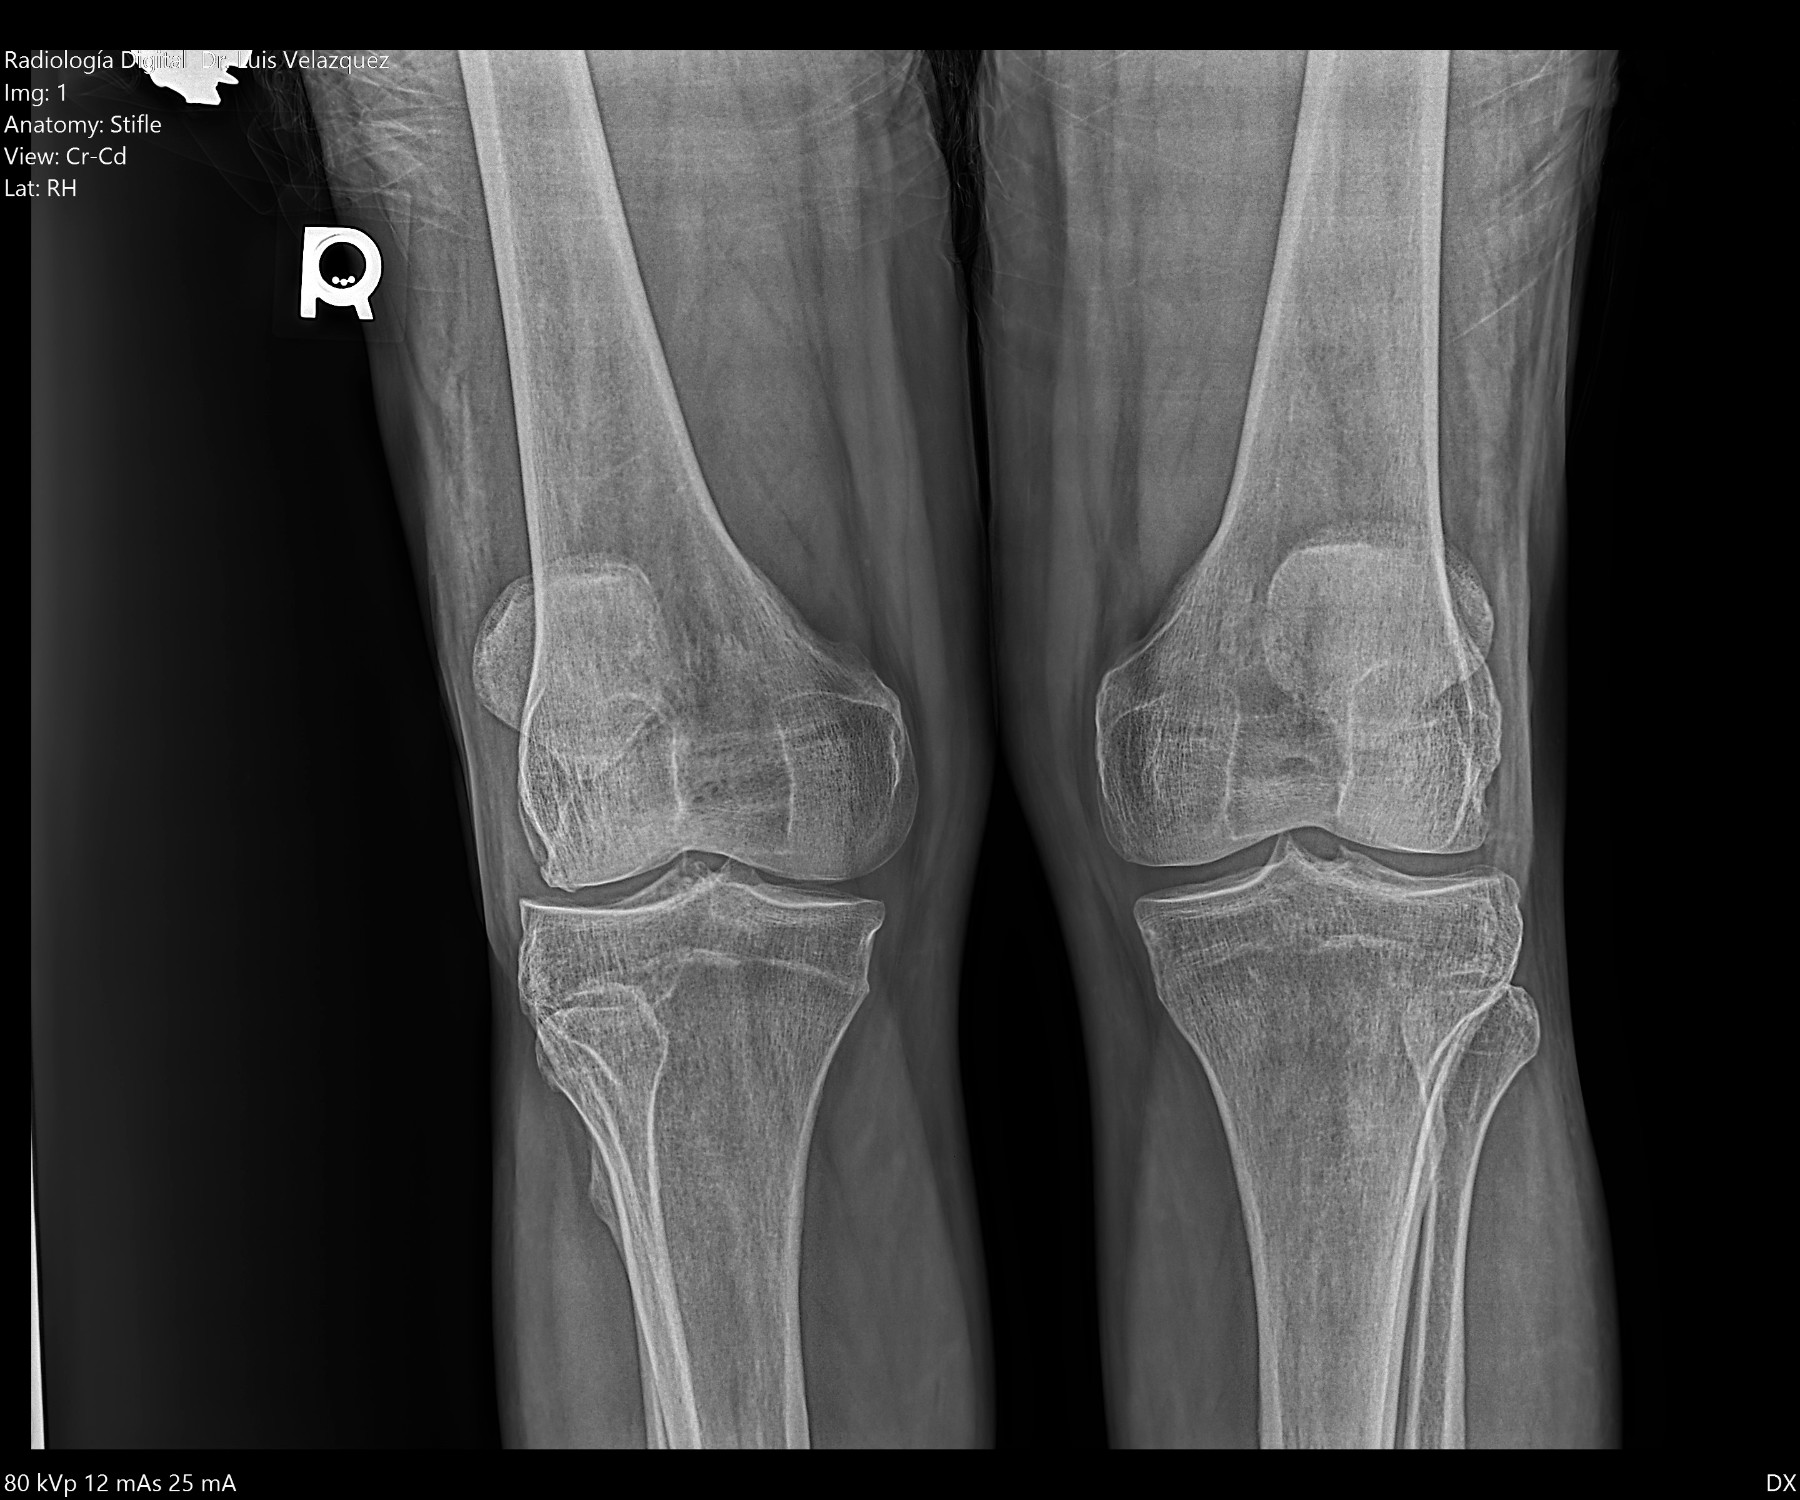

Cambios Térmicos en las Extremidades de Caballos,

Asociados a Golpes y su Evaluación por Termografía.

Los caballos de salto, en competencia, pueden derribar obstáculos y lastimarse. Si se golpean, no siempre claudican. Considerando al calor como un signo de inflamación, se evaluaron los cambios térmicos de 6 áreas de las extremidades torácicas y pelvianas de 23 caballos de salto en nivel de competencia de 1.05 a 1.60 m de altura, por medio de termografía durante 4 días de competencia (N=2208 áreas).